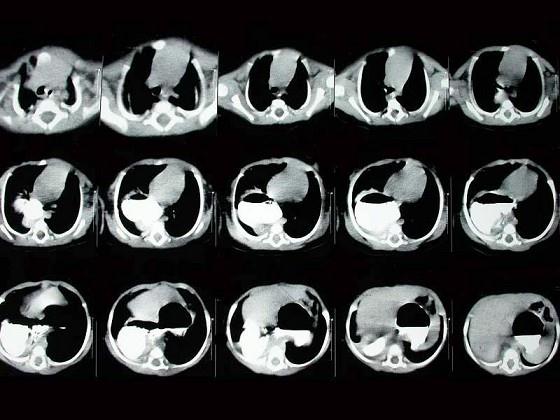

女,5岁,食欲差伴消瘦4年。如图所示,最可能的诊断为?(?)A.食道裂孔疝B.膈疝C.肺脓疡D.包裹性液气胸E.胃扭转

问题 女,5岁,食欲差伴消瘦4年。如图所示,最可能的诊断为?(?)

选项 A.食道裂孔疝 B.膈疝 C.肺脓疡 D.包裹性液气胸 E.胃扭转

答案 A